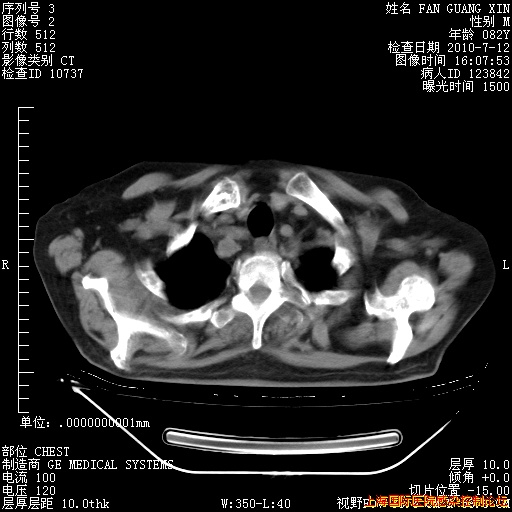

补发6月12日肺部CT肺窗

6月12日肺窗